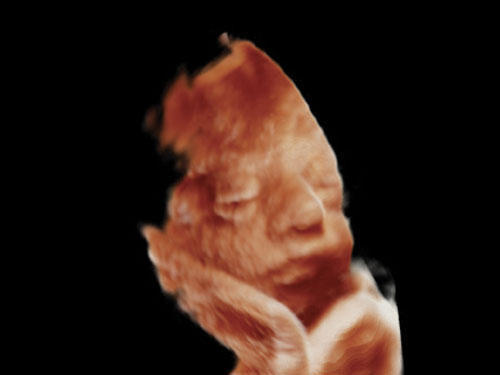

• Gynekologie

Konvexní a endokavitní sondy poskytují vynikající kvalitu obrazu pro aplikace v oblasti gynekologie a porodnictví. 3D konvexní sondu lze také použít pro standardní vyšetření.

XSTIC: Software pro rekonstrukci plodu XSTIC určený pro volumetrickou rekonstrukci v režimu B a barvě / síle srdečních dutin plodu.

AutoNT: Automatické měření nuchální translucence (NT).